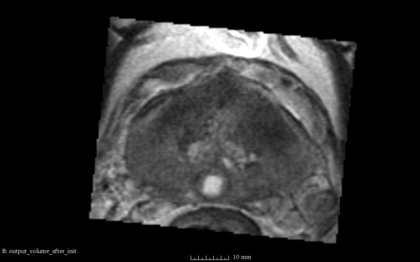

- the following images are shown from left to right:

- [1] Fixed Volume as Reference [2] SimpleITK result after Initialization [3] SimpleITK result after rigid registration [4] BRAINSFit result after rigid without using masks and --useCenterOfGeometryAlign

- The rigid registration result does not reasonable and is a little different with every computation. Reason might be that seed is set randomized and not set as done in BRAINSFit here. There is no option at the SimpleITK::ImageRegistrationMethod to set a metric seed.